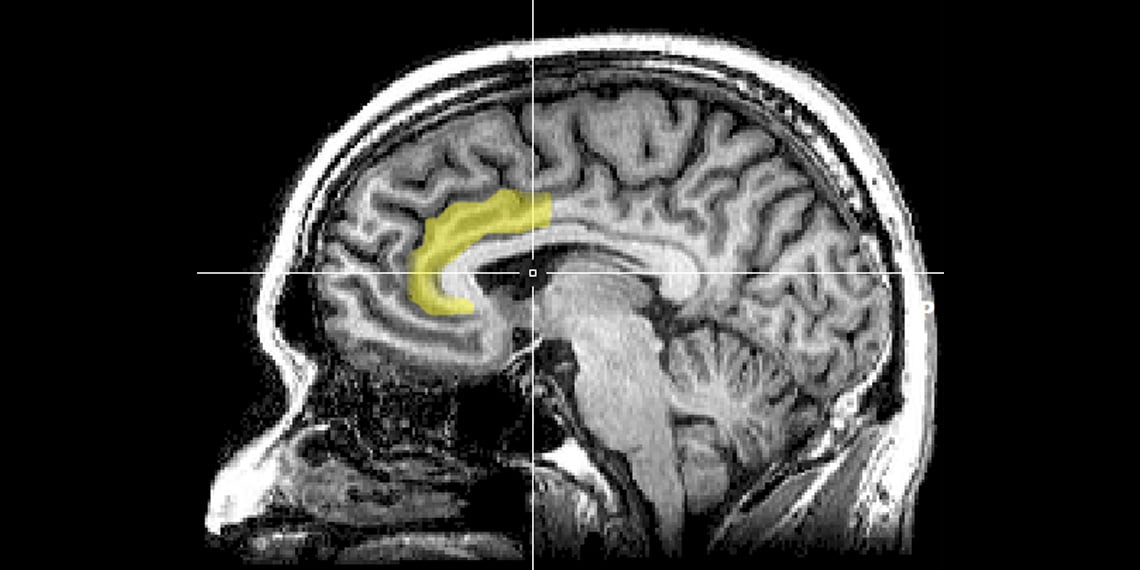

A new study using stereotactic electroencephalography (sEEG) sheds light on how individuals with treatment-resistant depression (TRD) process emotions differently due to abnormalities in the amygdala and prefrontal cortex, revealing heightened responses to negative stimuli and weakened responses to positive ones. Deep brain stimulation (DBS) shows promise in correcting these neural discrepancies, offering potential as a treatment method that could improve both positive and negative emotional processing in TRD patients.

New research delves into how ketamine affects brain connectivity in individuals with treatment-resistant depression, shedding light on its rapid antidepressant effects. The study, involving 50 participants, found that ketamine significantly improved depressive symptoms and the ability to anticipate pleasure compared to a placebo. Changes in brain connectivity within the anterior cingulate cortex were associated with improvements in depression and anhedonia symptoms, suggesting that different brain regions may contribute to these conditions in diverse ways. The findings provide valuable insights into the potential for targeted treatments for specific groups of patients burdened by particular symptoms.